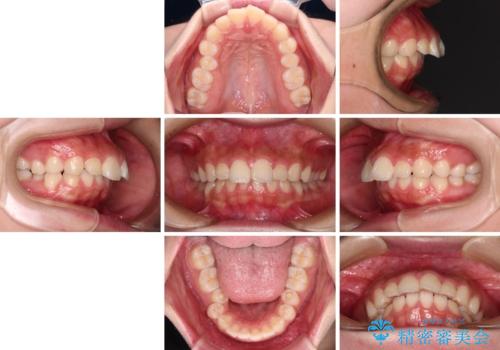

- 飛び出した上顎前歯と、閉じにくい唇、口元の突出した印象の横顔を気にして来院された患者様です。

骨格的な上顎前突であり、上下前歯の前後的な距離が大きいため、上顎は左右第一小臼歯を、下顎は左右第二小臼歯をそれぞれ2本抜歯することで前歯が接触するようにし、さらには奥歯の咬み合わせも、より理想的な状態へ近づけていくこととしました。